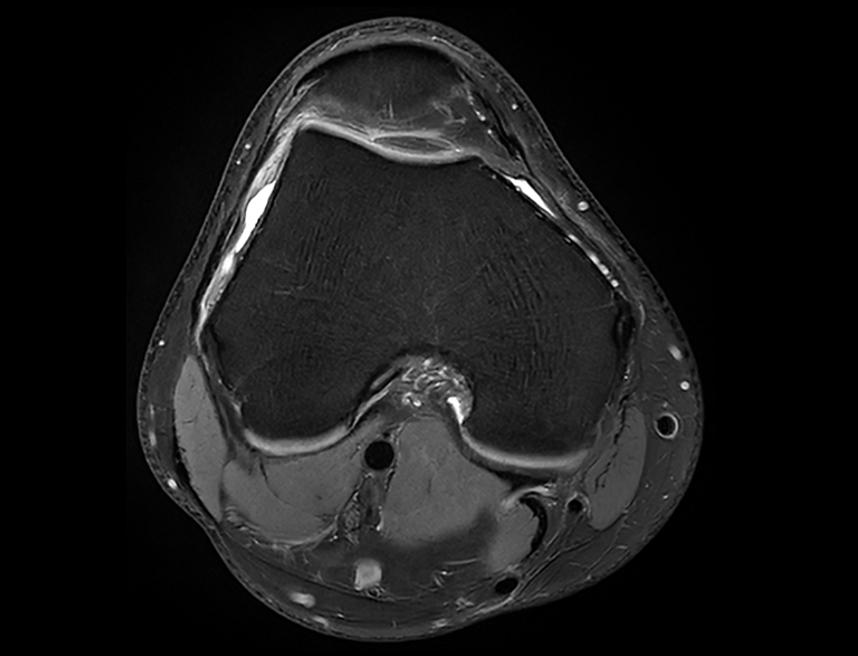

ACS (AI-assisted Compressed Sensing)는 United Imaging의 독점 MR 가속 솔루션으로 속도와 이미지 품질을 최적으로 균형있게 조화시키는 데 사용됩니다. CS, HF, PI를 결합하고 최첨단 딥러닝 신경망을 AI 모듈로 혁신적으로 도입하여 재구성 절차에 적용합니다. 이를 통해 사용자는 영상 품질을 향상시키면서도 검사 시간을 늘리지 않거나 이미지 품질을 저하하지 않고 검사 시간을 단축시킬 수 있습니다. 이는 더 완벽한 검사를 가능하게 하며, 영상의학과 전문의들의 진단가치를 높이고 환자의 편안함을 향상시킵니다.

MRI 영상에서 더 높은 가속 수준을 실현.

각 부위의 획득 시간을 100초 이내로 단축하여, 환자 처리량을 크게 향상시키고 움직임에 인한 아티팩트를 줄입니다.

작은 해부학적 구조물을 더욱 정확하게 묘사하여 진단 능력을 확장시킵니다.

MRI 검사를 견디기 어려워하는 노인, 소아 및 기타 특수 환자들에게 유용하여 검사의 성공률 증대.